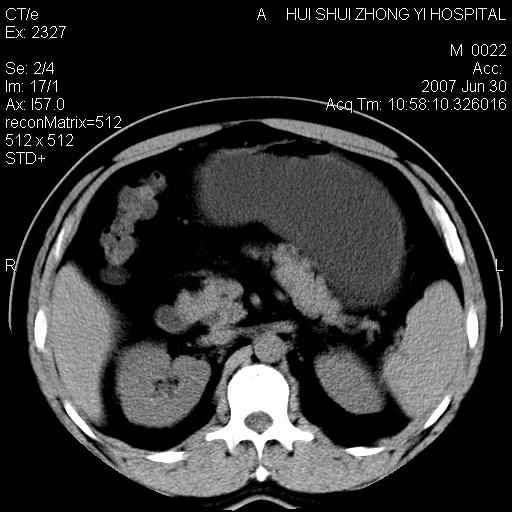

双肾结石

双侧肾盂、输尿管内结石,双侧肾脏轮廓呈波浪状,可能以前有过感染的

支持双肾结石

支持双肾结石,肝右叶低密度影为胆囊部分容积效应。

双肾结石.

双侧肾盂结石。

病人呼吸动了,第四层应该在第五\\六层之间。肝右叶低密度影为胆囊部分容积效应。双肾结石。

双肾结石,少量腹腔水?

2、双侧肾盏结石。